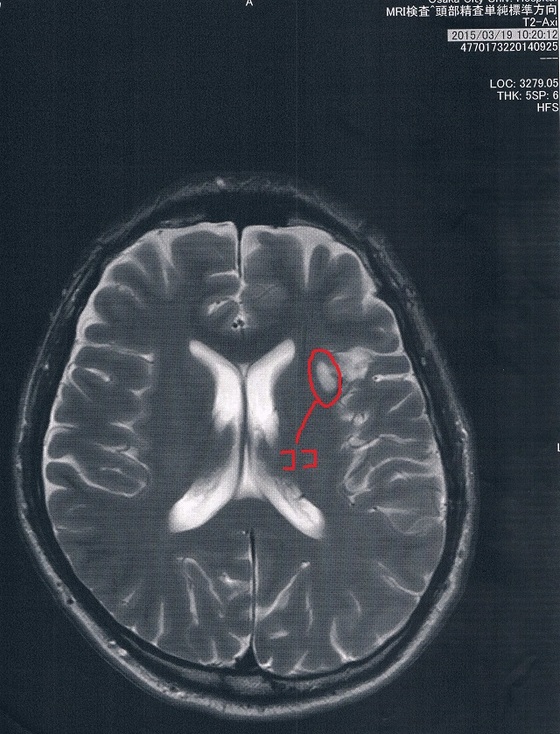

2015/3/19(手術後9か月)のMRI画像